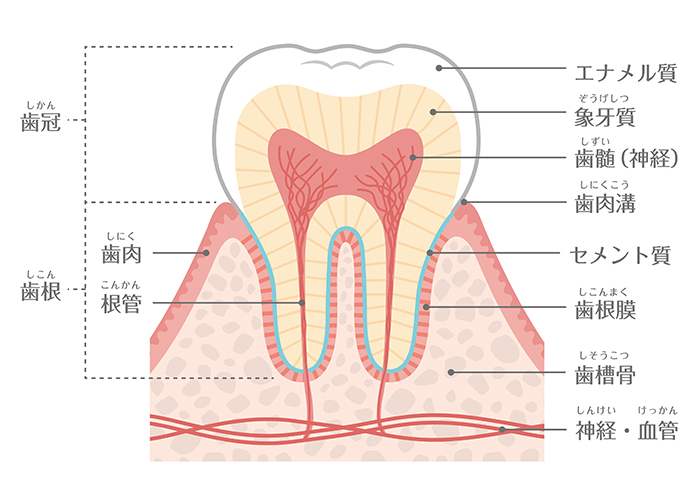

歯周組織は歯肉(歯茎)と歯槽骨(歯を支える骨組織)、歯根(歯の根元)を覆うセメント質、歯根と歯槽骨をつなぐ歯根膜からなります。